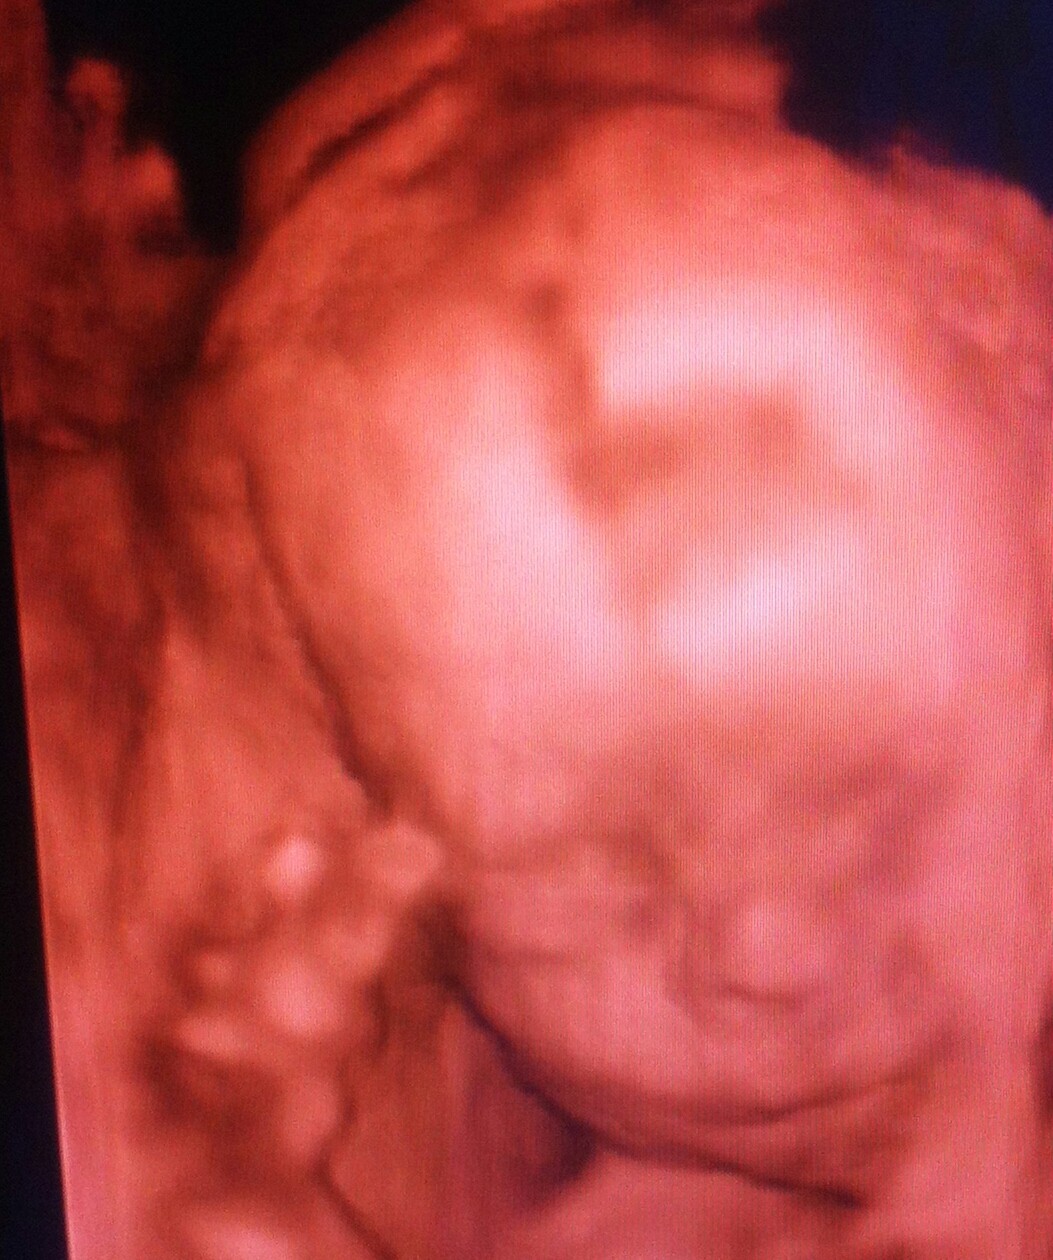

Hej cioteczki. Michalinka chciała się z wami przywitać :)

IMG_3314-1.jpg